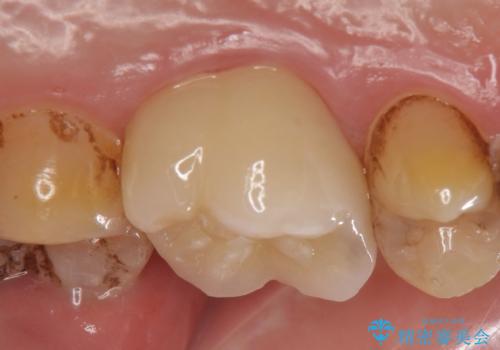

- ものを咬むと左上の奥歯が痛むので診て欲しいといらっしゃった方の症例です。

診査の結果、左上6が失活(歯の神経が死んでいる状態)しており根尖病変を認めたため、根管治療を行いました。

根尖病変の縮小及び症状の消失を確認後、オールセラミッククラウンによる補綴を行いました。